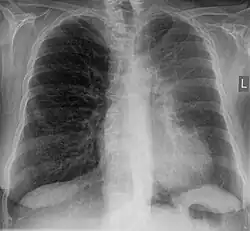

Bei der Perkussion hört man eine Dämpfung des Lungenschalls. Bei der Palpation besteht eine Abschwächung des Stimmfremitus.[3] Das Atemgeräusch ist bei der Auskultation der Lunge abgeschwächt. Im Röntgenbild des Thorax sind als direkte Zeichen eine Transparenzminderung und Verlagerung der Lappenspalten sowie als indirekte Zeichen ein Zwerchfellhochstand, eine Mediastinalverlagerung, ein kompensatorisches Emphysem, eine Hilusverlagerung und eine Engstellung der Rippen zu sehen. Differenzialdiagnostisch muss an eine Pneumonie gedacht werden, Atelektasen zeigen im Gegensatz zu dieser kein Bronchopneumogramm. Alternativ oder ergänzend zum Röntgenbild kann man eine Computertomografie-Aufnahme anfertigen. Im Ultraschall sieht man Atelektasen im Bereich eines Pleuraergusses als nicht belüftete, volumenverminderte Lungenabschnitte.